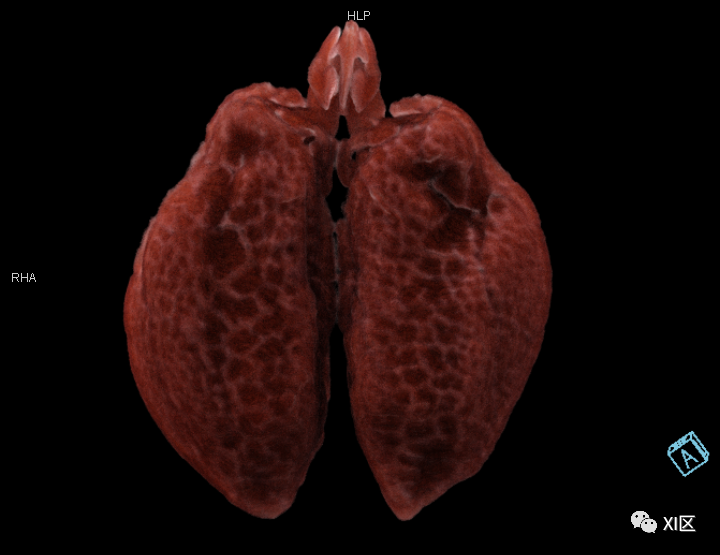

牛蛙肺部重建

作为对比,人类的肺部重建 SOMATOM Force扫描 cVRT重建

人类胸部Cinematic Rendering重建

第二,

我们仔细观察了牛蛙的肺结构

不同于人类

牛蛙的两肺气管很粗大

直接和声门相连

气出来的更顺利